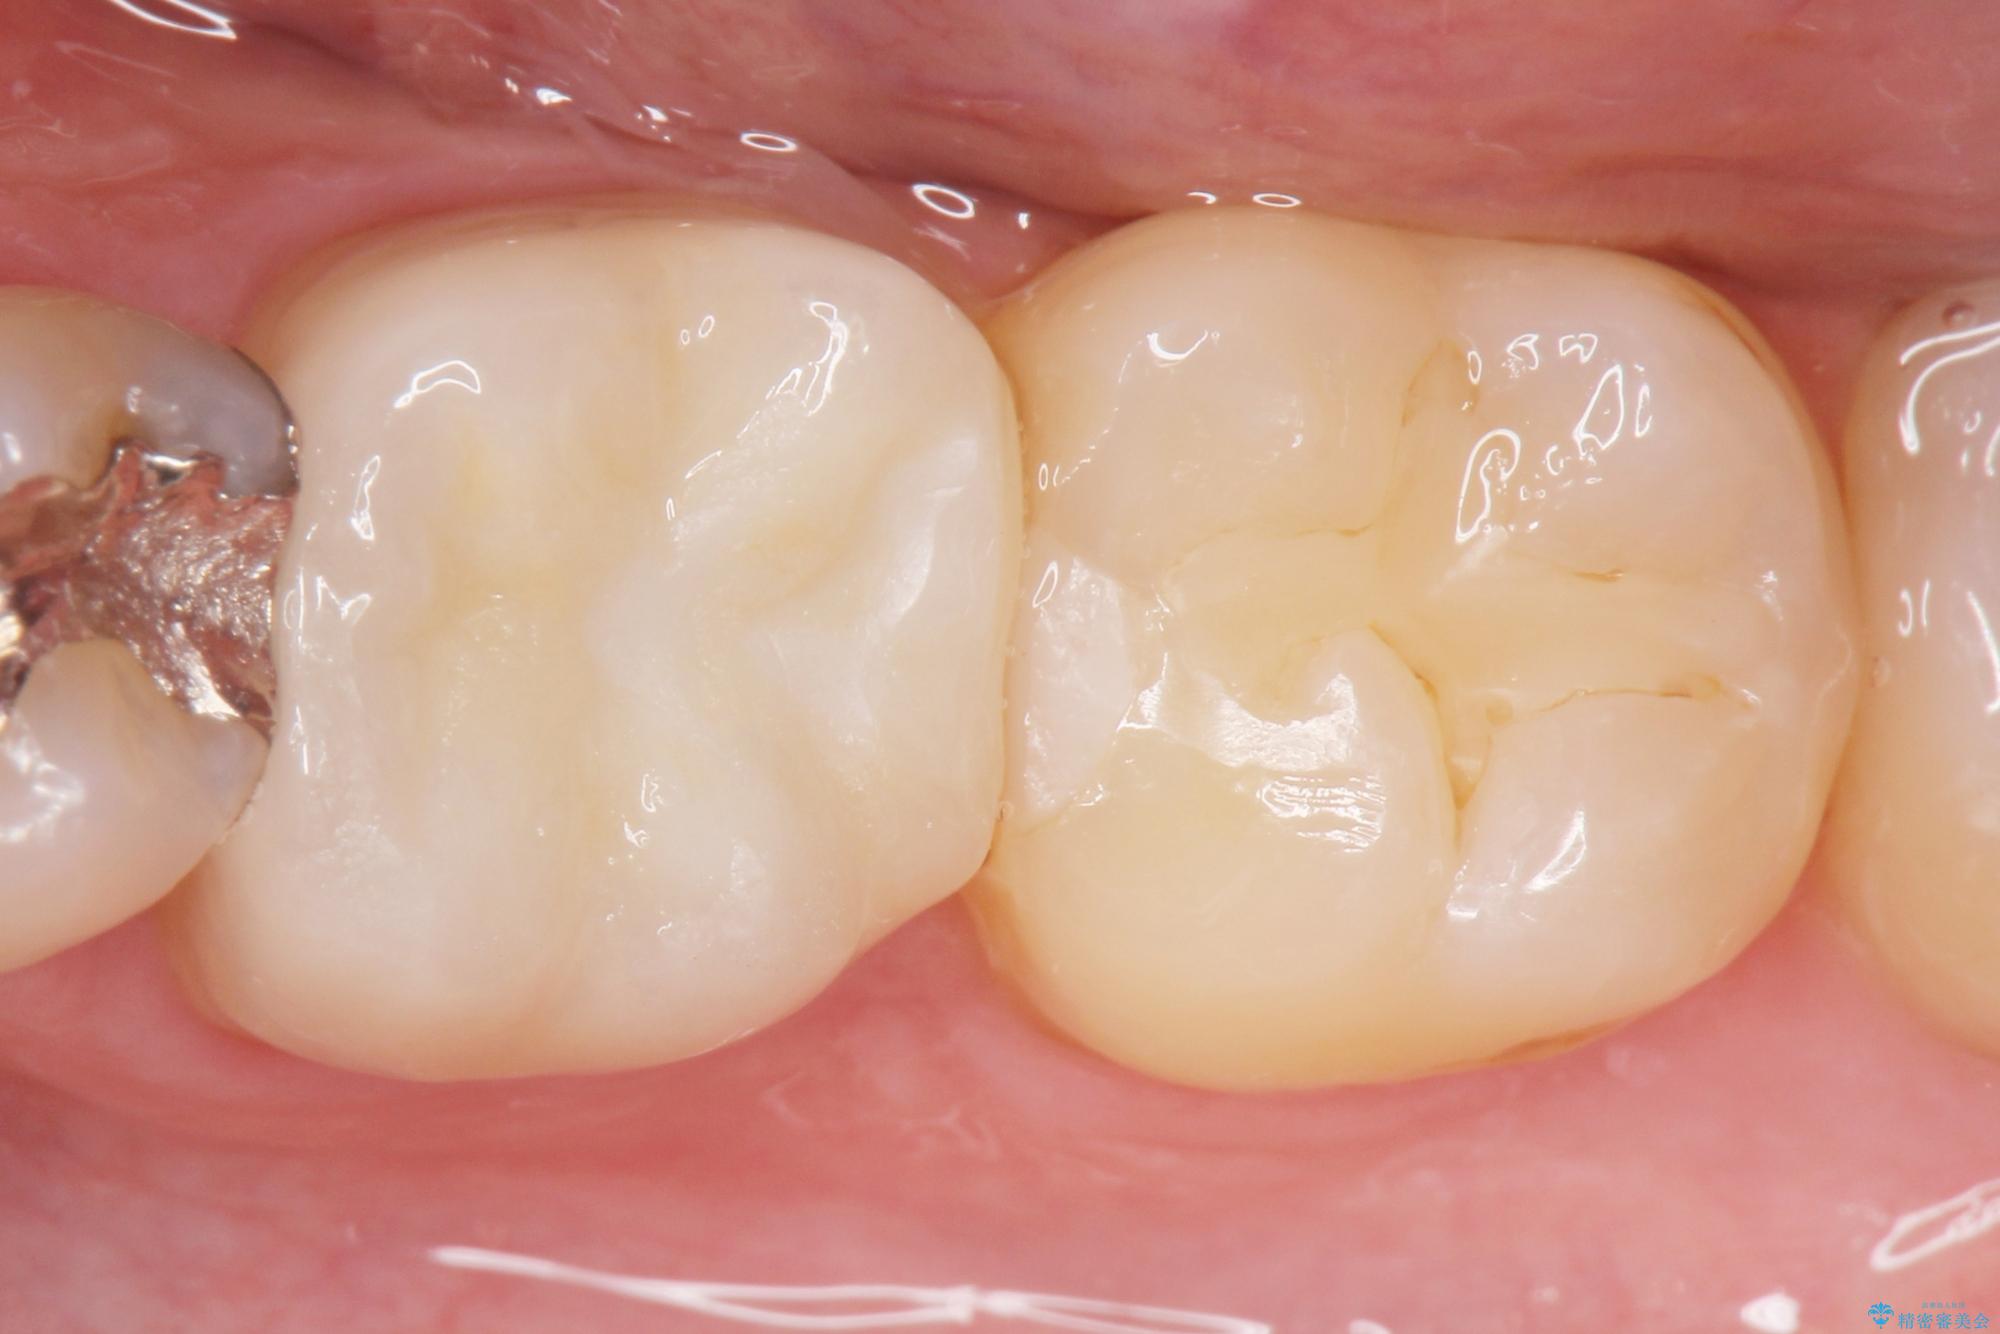

適合の悪い銀歯をセラミックへ

食べ物がよく詰まる、見た目も悪いので銀歯をやり替えたいとご来院された患者様です。

治療後について

歯と歯の間に食べ物が詰まったままの状態だと、虫歯や歯周病を誘発しやすいため、注意が必要です。